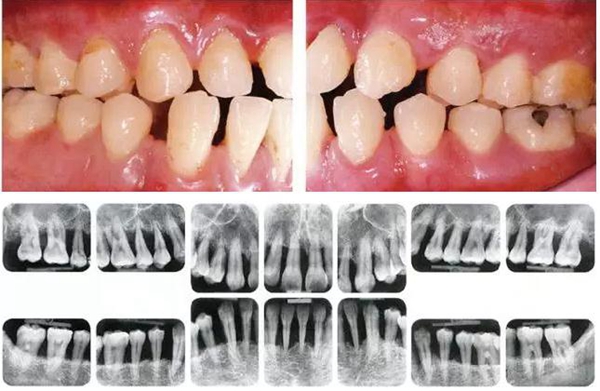

●參考病例② 25歲女性

25歲女性。菌斑控制狀態(tài)不好。齦溝除磨牙處外全在3mm以下,X光照片上左上、右下、左下的第一磨牙上有垂直性骨吸收。這個(gè)病例是參考病例①10年前的狀態(tài),是典型的侵襲性牙周炎局部型。